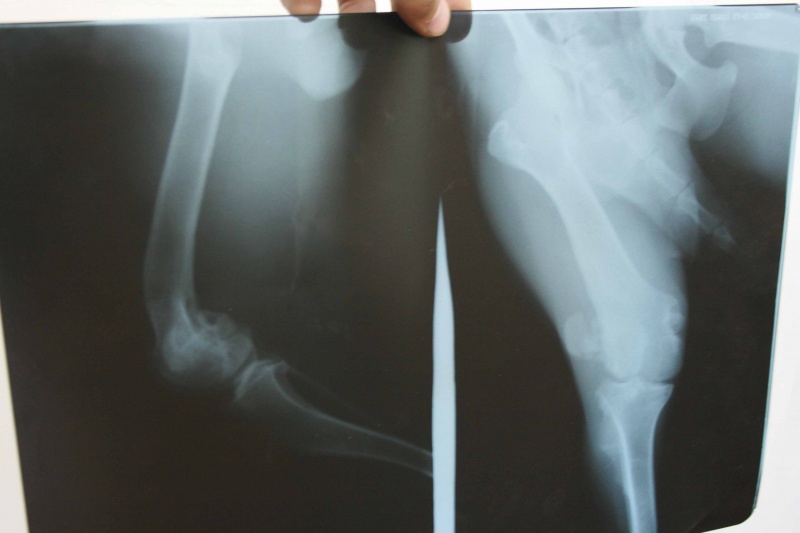

Аля - красивая молоденькая собака, почти еще щенок, доверчивая, ласковая, не зашуганная. Но если она останется инвалидом, ее шансы на пристрой будут стремиться к нулю, да и искалеченная лапа явно причиняет ей боль. Скорее всего, у собаки либо вывих, либо перелом коленного сустава. Для начала мы повезем Алю на ренген к Козлову, возможно, позже потребуется операция. Очень просим финансовой помощи форумчан: Аля не должна остаться инвалидом... Пока что нужно около 700 рублей на ренген.

, целыми днями мотаюсь по делам приютским. Как только смогу, вас наберу обязательно. Эти 500 рублей частично покроют оплату ренгена (он стоил 700 рублей), как только заберу от вас деньги, сварганю отчет. Фото ренгена и чека тоже выложу на днях.

. То бишь перед медуходом и рисками. Собственно, поэтому и жду советов форумчан. Есть ли смысл делать песе сложную операцию, в результате которой она, возможно, станет здоровой, или не маяться дурью и просто ампутировать лапу? Склонялась к последнему...но вспоминаю эту доверчивую мордаху, отчаянно виляющий хвост, преданные глаза...и отметать имеющийся шанс и делать ее инвалидом? Резко урезать не только здоровье, но и шансы обрести хозяев? Не знаю... Кто что думает по этому поводу?